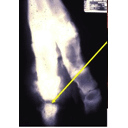

Septic Arthritis Radiograph.jpg